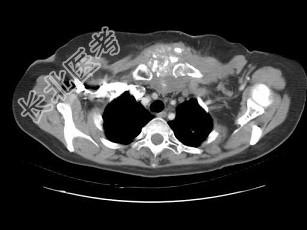

- 单项选择题女,46岁, 胸痛,乳腺癌放、化疗术后, 结合图像,最可能的诊断是 ( )

B、胸骨坏死